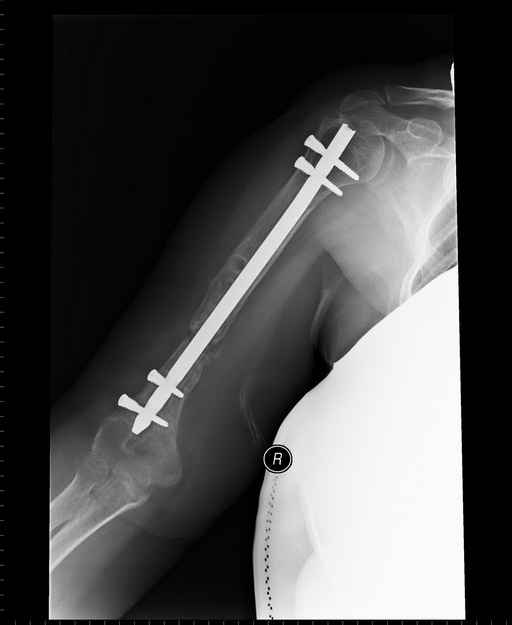

Больная 48 лет, медсестра-массажист, перелом плеча 7 лет назад, оперирована 4-кратно и безуспешно

Больная 48 лет, медсестра. Травма получена 7 лет назад, оперирована первично в Турции - остеосинтез пластиной - несращение - реостеосинтез стержнем там же через год (обычным, с выстоянеием его в полость плеча) - несращение - поступила к нам впервые в марте 2008 года - удаление стержня, реостеосинтез пластиной и костная пластика, в течение 2 лет лизис кости вокруг винтов, смещение фиксатора, в марте 2010 - удаление пластины, реостеосинтез интрамедуллярным стержнем с блокированием (рассверливание + костная пластика). В динамике - вновь лизис в области перелома, нестабильность дистальных блокирующих винтов.

Клинически фиксация пока действительно стабильна, но на рентгенограммах резорбция кости в области дистальных блокирующих винтов и миграция одного из них.